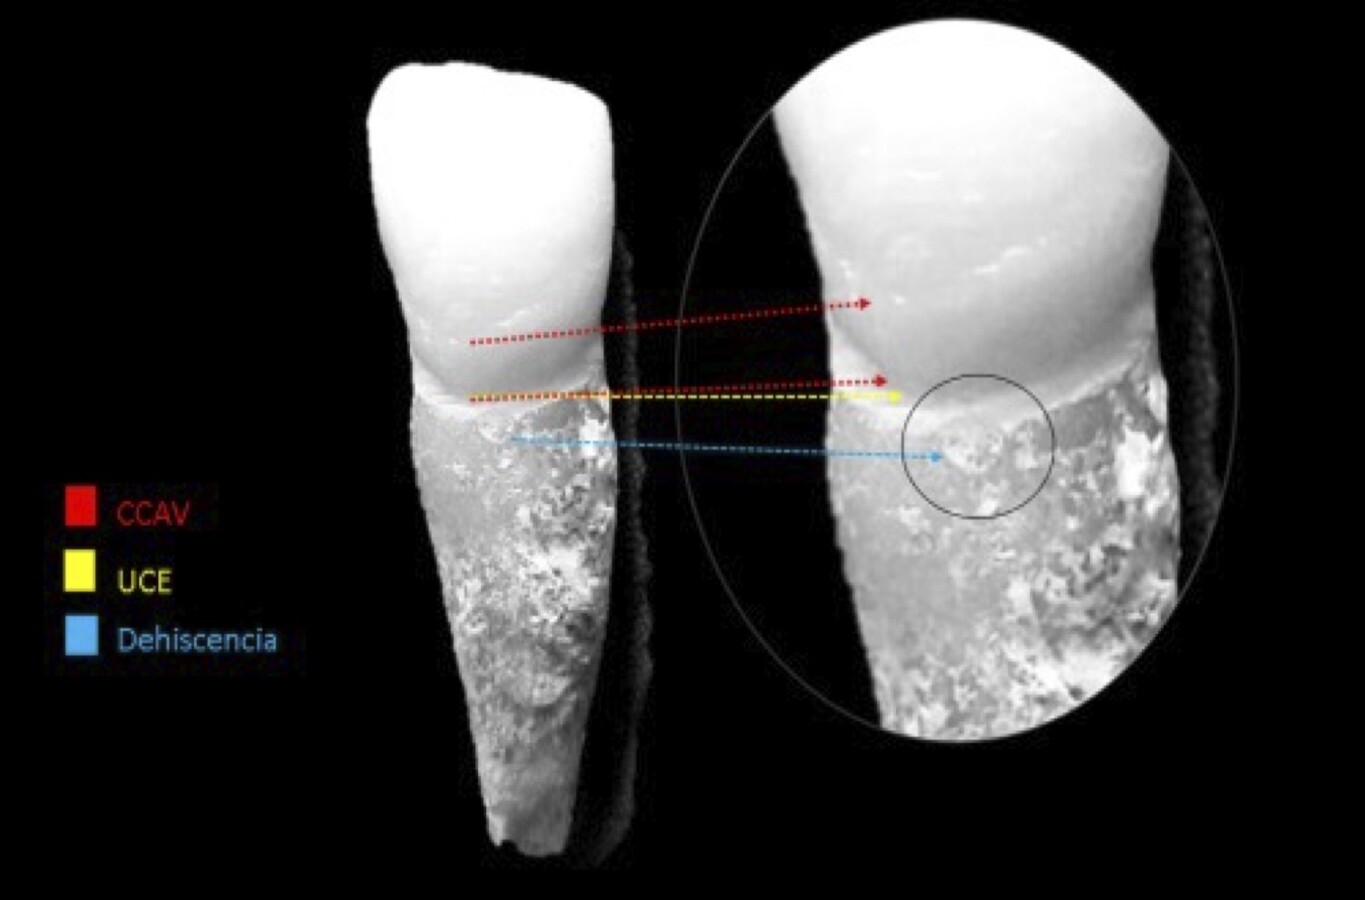

Figura 2. A) Paciente 14 años con cinturón cervical. B) Paciente de 18 años, con cinturón cervical e influencia de desmineralización.

Figura 3. Delimitación del cinturón cervical adamantino vestibular (rojo). Unión esmalte-cemento (amarillo). Rasgos sulculares en diente anterior, líneas incrementales formulando dehisencia (azul)